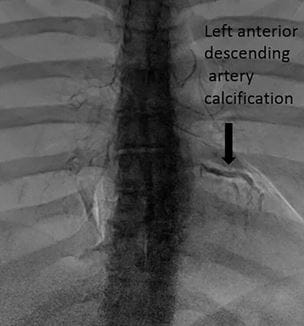

New Imaging Techniques to Identify Coronary Disease

Can a common chest x-ray help detect heart disease? - Innovations in Cardiovascular Medicine & Surgery | Summer 2019

Making the Case for CT CORONARY CALCIUM SCORING

Harrington Heart & Vascular Institute Innovations | Spring 2016